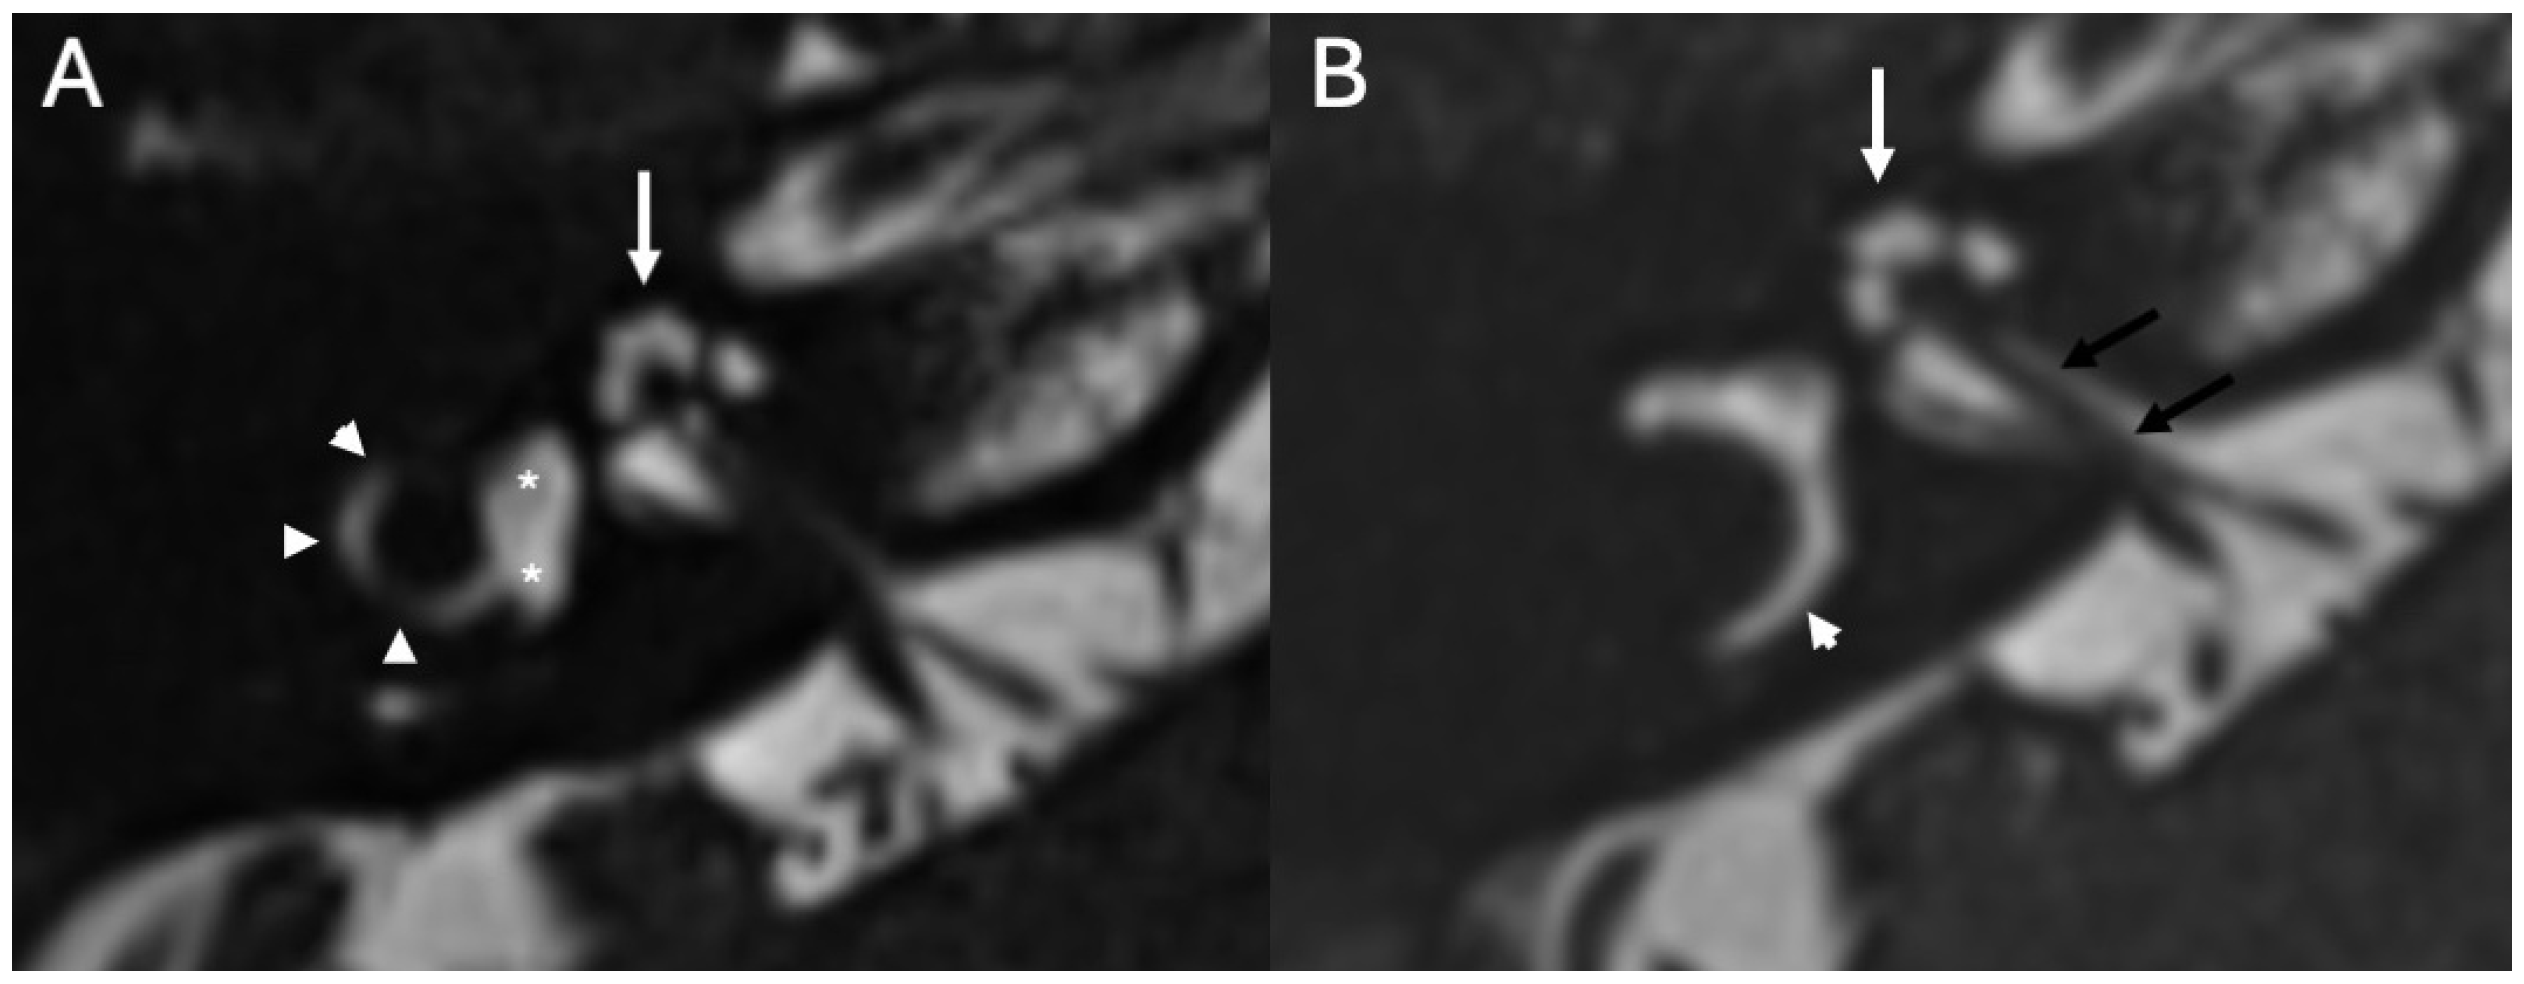

3.2. Bony Dehiscence

| Bony Dehiscence/Temporal Bone Defects | Barbara et al., 2022 [22]; Sanna et al., 2009 [23]; Lim et al., 2012 [24]; Rabiei et al., 2025 [25] | Case-based studies and reviews | Tegmen tympani or semicircular canal defects create a route for meningitis and meningoencephalocele; HRCT coronal reconstructions preferred. |